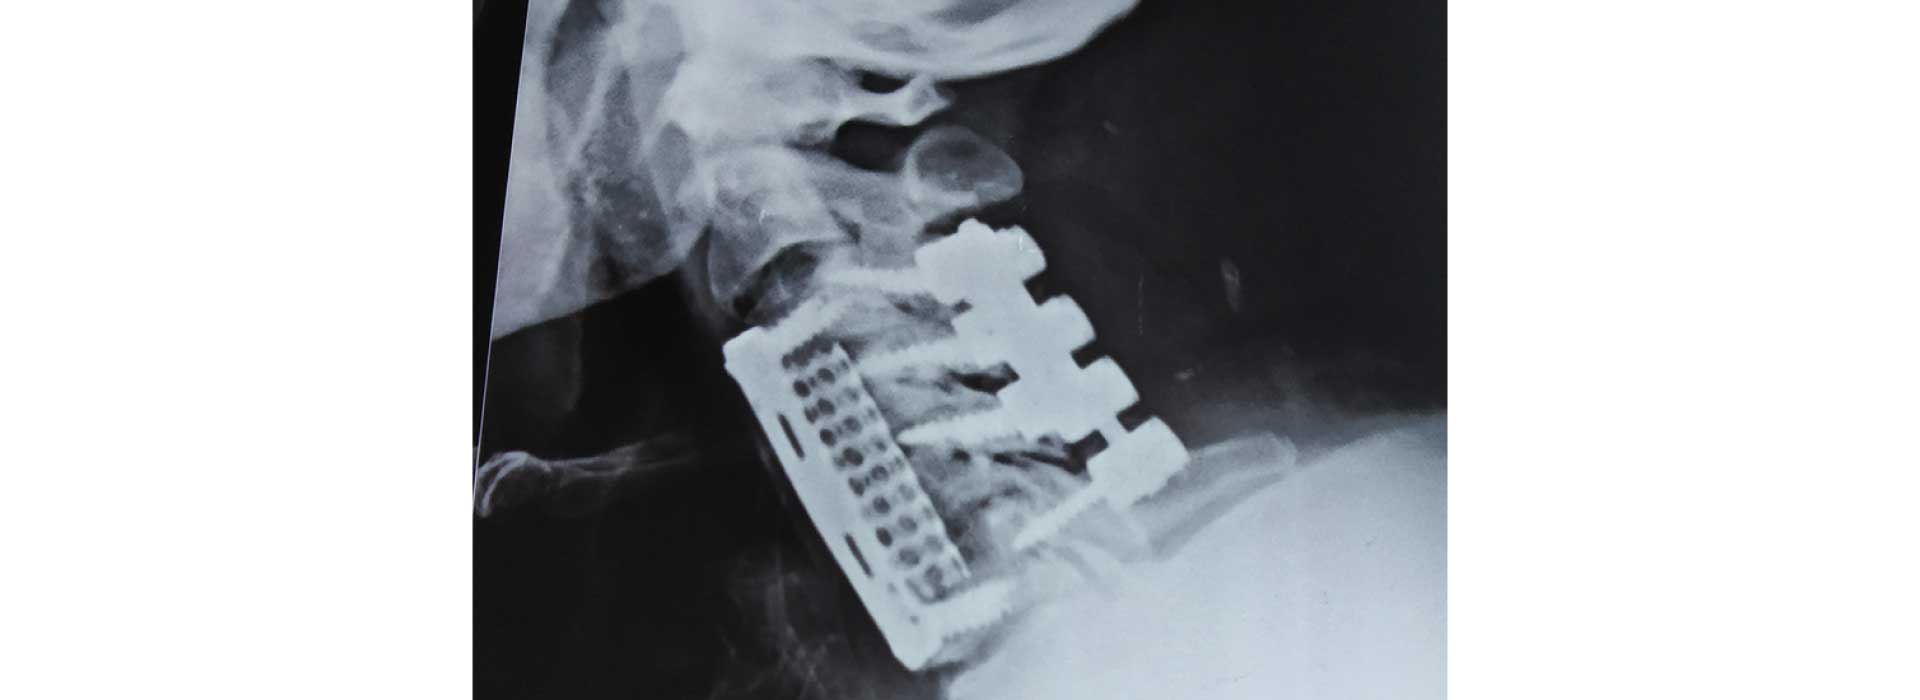

All kind of simple and complex surgery for cervical, dorsal and lumbar spine